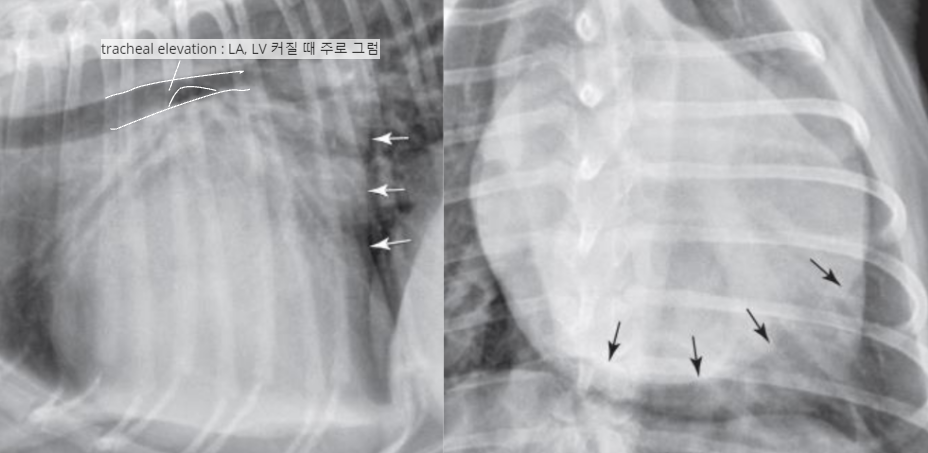

| Generalized cardiomegaly |

| RA, RV, LA, LV๊ฐ ๋ค ์ปค์ง โ Globoid heart |

| - Pericardial effusion - ์ฌํ ์์ชฝ ์ฌ์ฅ๋ณ (MVI + TVI) - PPDH (Peritoneopericardial diaphragmatic hernia) - Cardiomyopathy (DCM) - Anesthesia, bradycardia |

![]() |

| Microcardia |

| ICS < 2.5 |

| Hypovolemia, shock, dehydration, Addisonโs dz, Canine hypoadrenocorticism ๋ฑ |